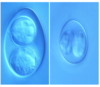

Coccidiosis of ruminants

Oocysts in a camel

Thicker walls seen for survival in desert like conditions

Coccidiosis of ruminants

Oocysts in a camel

Thicker walls seen for survival in desert like conditions

Eimeria

Eimeria Cameli

Thick wall with well seen cap

Eimeria Cameli

Thick wall and well seen cap